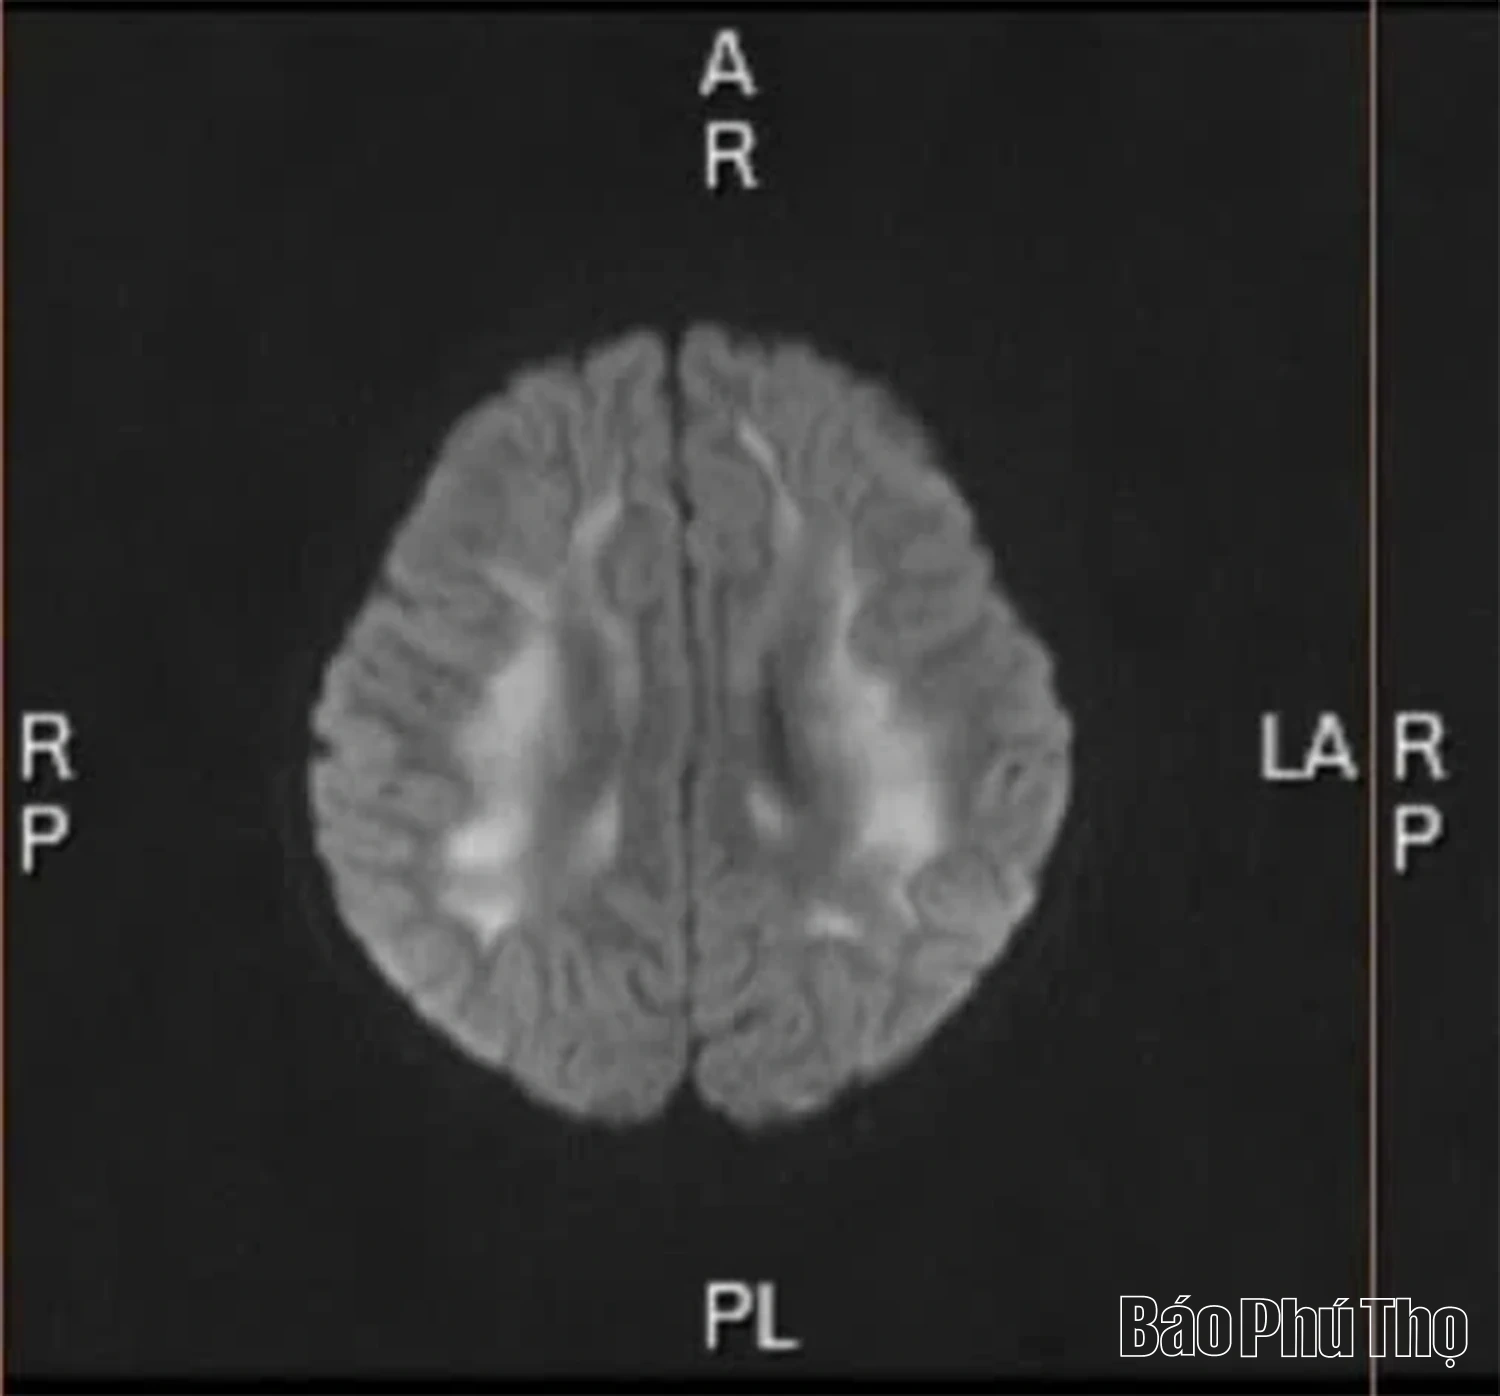

Hình ảnh chụp cộng hưởng từ não cháu bé 6 tuổi bị tổn thương do ảnh hưởng từ khói thuốc lá điện tử

Theo bác sĩ chuyên khoa, nicotine và các tạp chất trong thuốc lá điện tử có thể gây co thắt mạch máu não, giảm lưu lượng máu nuôi dưỡng, hình thành huyết khối và viêm mạch. Với não bộ của người trẻ đang trong quá trình hoàn thiện, sự tác động này gây suy giảm trí nhớ, khả năng tập trung, rối loạn kiểm soát hành vi và cảm xúc. Một số trường hợp ghi nhận tổn thương chất trắng não, viêm não độc chất, phù não, co giật hoặc đột quỵ ngay cả khi còn rất trẻ.